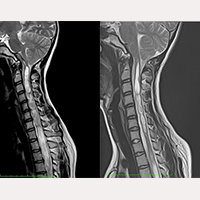

SFT nach subokzipitaler Kraniektomie (SOK)